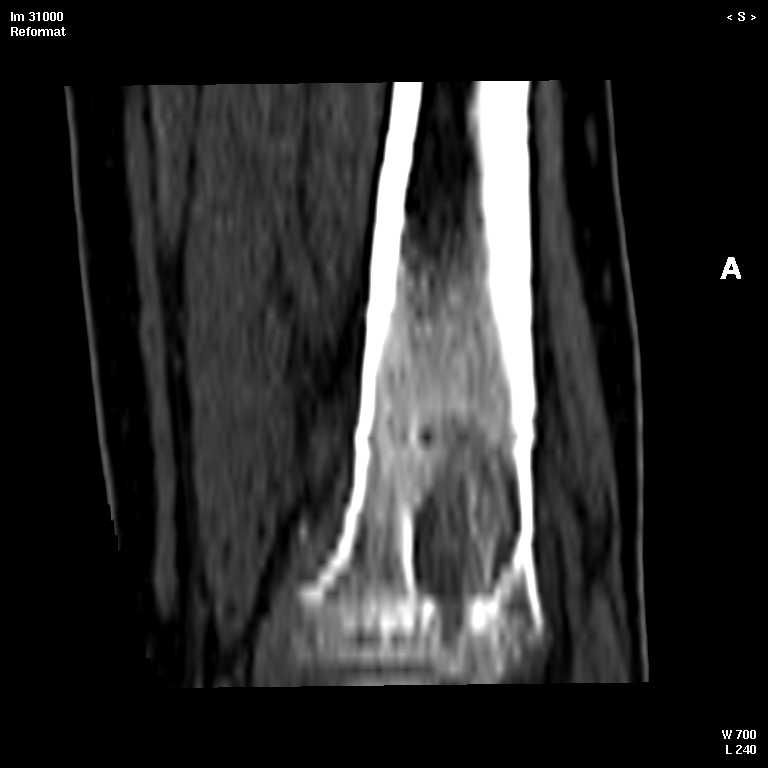

КТ изображения передаю на мой взгляд самые демонстративные. Их любезно записал коллега,

проводивший исследование в другом городе.

Прошу прощения за немного некоректную отправку КТ-снимков но по другому не получается :)

7